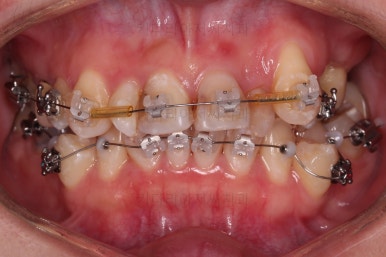

사용한 장치 : 자가결찰 세라믹(엠파워 클리어, Empower clear) + 미니스크류

덧니를 개선하기 위해서 추가적으로 작은 어금니를 발치했고요.

이 때 발치하게 된 치아는 가장 약한 치아, 치료가 많이 되어있거나 치료가 필요한 치아 위주로 선택하게 됩니다.

아랫니는 많이 삐뚤긴 했지만 옆라인, 턱의 크기 등 모든 걸 종합적으로 판단해 비발치로 진행하기로 했습니다.

물론 윗니 이미 없었던 치아 부분은 공간을 모아서 임플란트를 하지 않도록 하는게 목표였고요.

치열은 매우 가지런해졌고요.

추후에 발치 공간을 모아나가야 합니다.

윗니 앞니는 급한대로 신경치료 부터 진행했고, 최종 심미보철은 교정 후 미루었습니다.